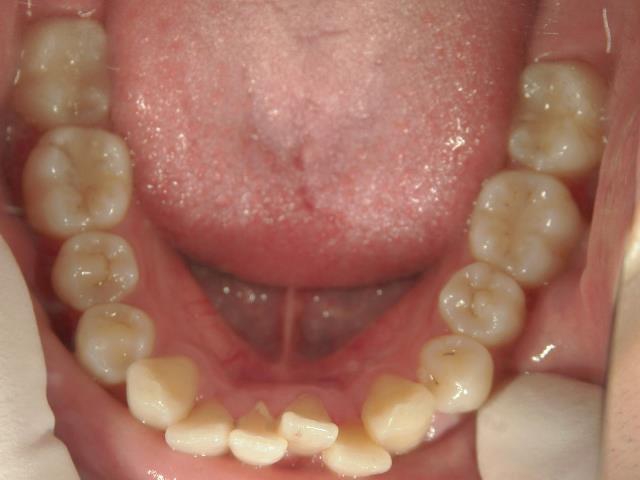

矯正歯科 治療前